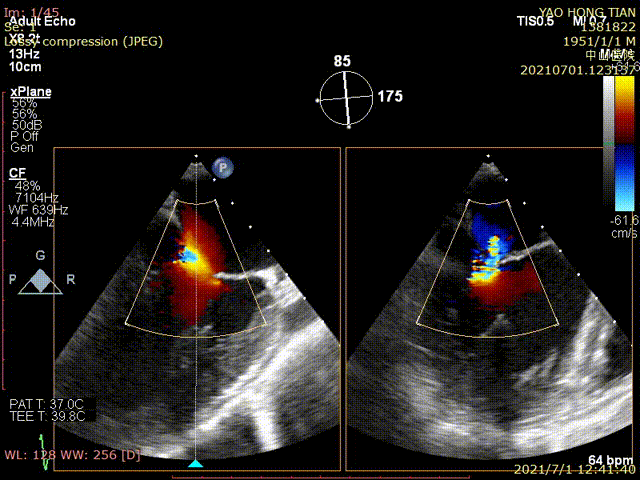

图1为一例患者的术前术后图像

术后超声